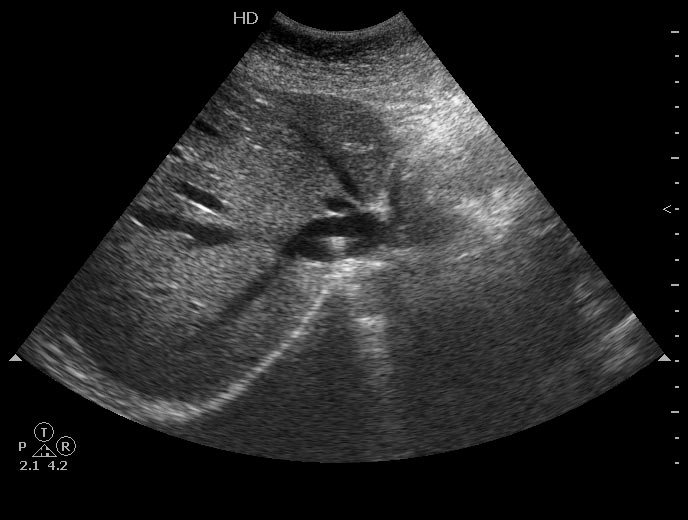

УЗИ: обломок электрода искусственного водителя ритма в НПВ

Женшина с жалобами на боли в животе поступила в хирургическое отделение. Боли локализуются в эпигастральной области, непостоянные.

Температуры нет.

в нижней полой какое то эхогенное включение... :shock: ну тромб наверное, что ещо то...

Инородное тело нижней полой вены... Возможно, электрод искусственного водителя ритма... А какие оперативные вмешательства в анамнезе?

marusja писал(а):Инородное тело нижней полой вены... Возможно, электрод искусственного водителя ритма... А какие оперативные вмешательства в анамнезе?

Он, родимый.

Поставили со второго раза, первый обломался.